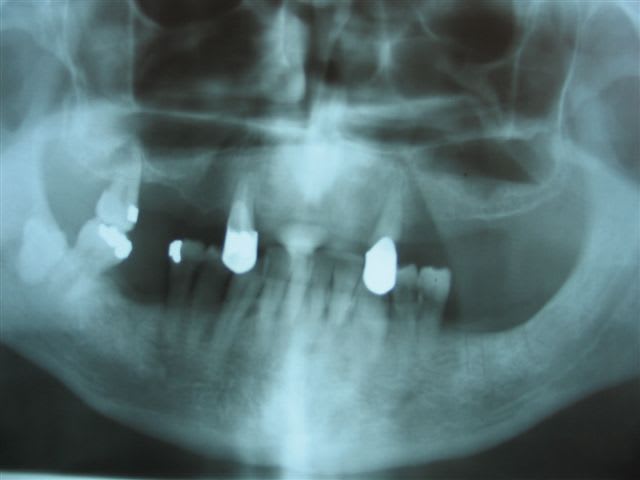

mes 2 derniers cas implantés sont

*1 maxillaire avec 5 NP de 10mm en bi-cortical sous les fosses nasales+bio oss/biogide pour refaire la crete (3.5mm d' os) ,

*et 6 implants à la mandibule, dt 5 entre les mentonniers (4 rp x 16mm + 1 rp x 13 mm) et un RP de 10 mm avec col non enfouis avec un dentaire à 10mm...

soit j' attire les cas peu simples, soit je trouve peu simple des cas simples, soit je ne suis pas une bonne chirurgienne et je fais passer des scan pour rien...mais pour ces chir, je ne vois pas comment decemment, on peut se passer d' un scan, et d' un pdv médico-légal, je vous souhaite de ne jamais perforer une corticale linguale ds la zone mentonnière ou d' avoir des paresthésies définitives sur un avocat!!!!!

Bon, des implants, j'en ai jamais fait, mais comme je vais faire une formation en octobre, je recherche des cas, notament pour la chir assistée.

Voici donc un patient que je vois pour bilan, souhaite refaire stellite haut, n'a jamais rien eu en bas et ne veut pas de mobile en bas.

Des implants de 8x5 ( je savais même pas que cela existait ! ), c'est possible ?

(2 a gauche, et 1 à droite, ou bridge à droite )